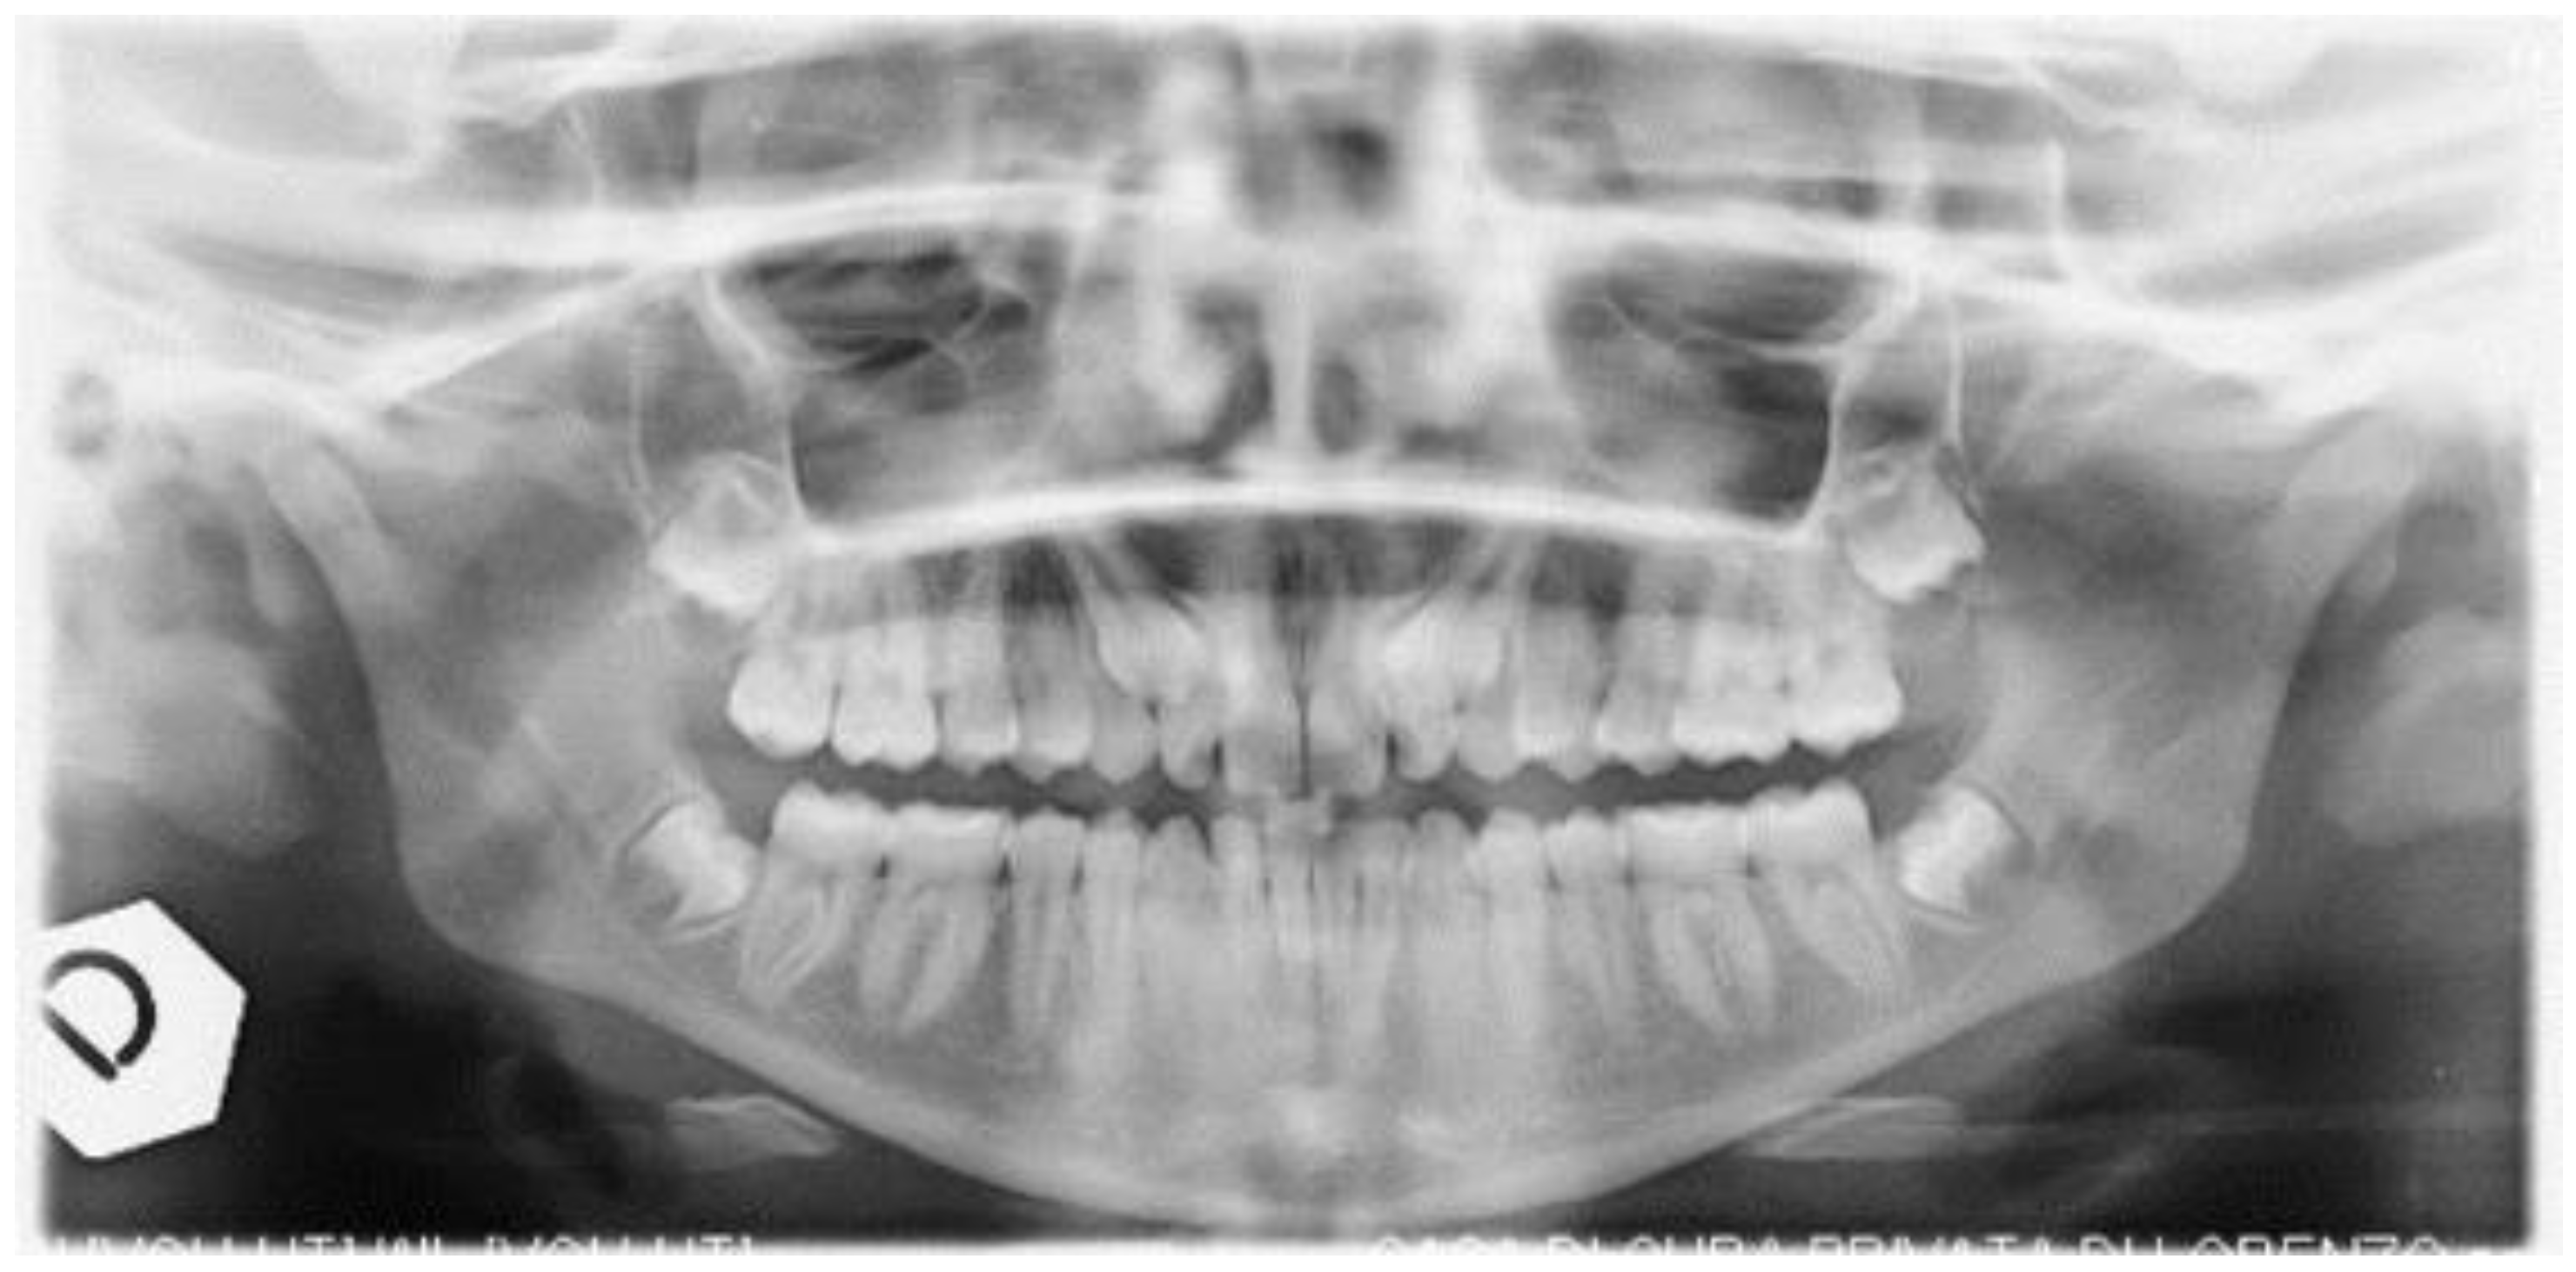

Uncovering and Autonomous Eruption of Palatally Impacted Canines—A Case Report

2. Case Presentation